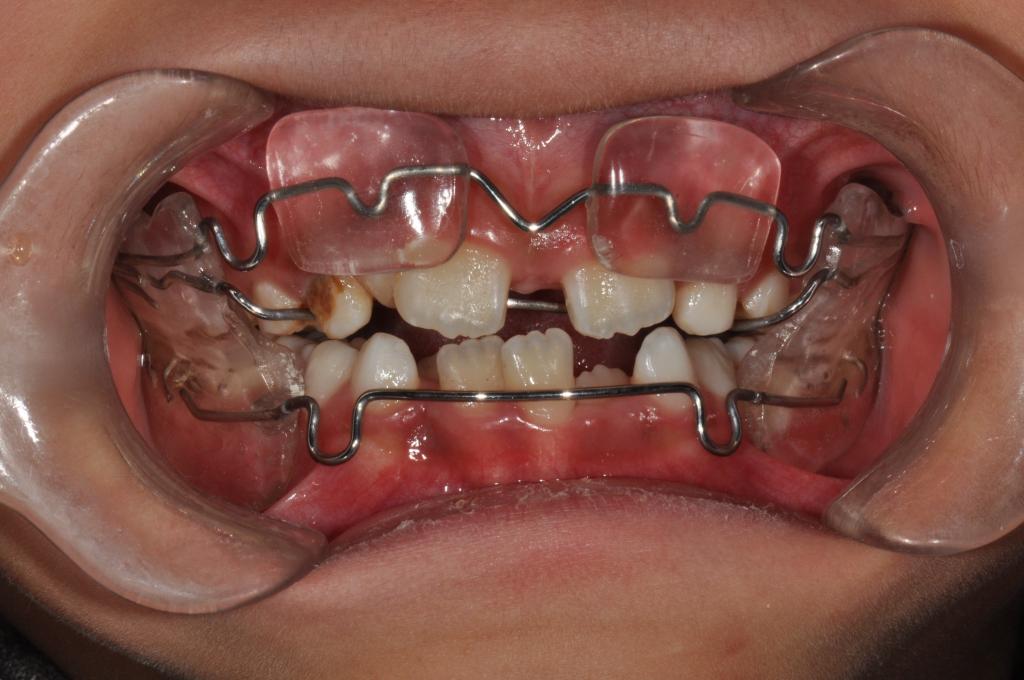

① 合垫舌簧矫治器

② 前方牵引矫治器

③ Frankel Ⅲ矫治器